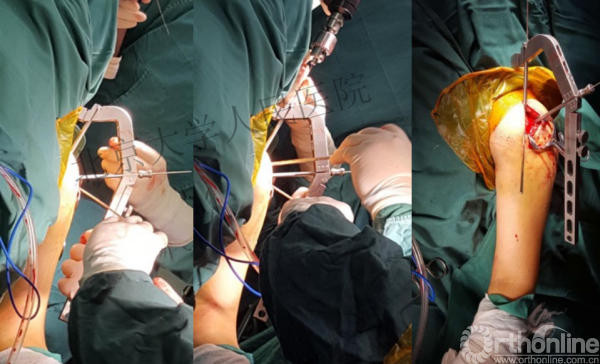

进钉更完美——我们的帮助

术中片

克氏针的应用“joystick”

简单骨折的闭合复位技术:以克氏针作为“joystick”

髓内钉的应用复位是关键